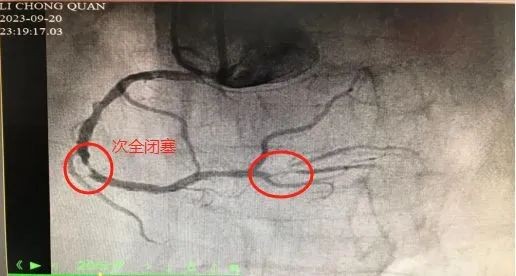

术中,冠状动脉造影提示李爷爷冠状动脉病变严重:左前降支近段,左旋支近段、中段以及局部,右冠脉近段、中段三支血管均出现了程度不一的病变,狭窄程度最高达90%。其中,右冠脉弥漫性粥样斑块形成,后降支近段次全闭塞。

▲术前造影图像